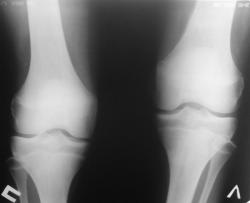

Мальчик 15 лет. Несколько месяцев назад начали беспокоить боли в коленных суставах. Травмы не было. Ребёнку был выставлен диагноз: болезнь Шлаттера, назначено лечение. На фоне лечения отмечалось значительное усиление болей, боли локализовались в левом коленном суставе. При дообследовании выявлена следующая рентгенологическая картина. Наши рентгенологи настаивают на срастающемся переломе. Но: 1) перелом без травмы? 2) бедро так не ломается

Линейный периостит, уже должен был рентгенологов насторожить.

Локальный гиперостоз, выраженный болевой синдром, структура губчатого вещества диафиза не изменена наводит только на остеойд-остеому.

Я бы на первое место поставила патологическую перестройку, так называемый, стрессовый перелом. Мальчик чем-нибудь занимается?

Согласна с Ola-la - рентгенологическая картина более всего соответствует стрессорному перелому, хотя для него характерна локализация в б/берцовой кости. Меня однако, смущает и настораживает клиника - это как раз тот случай, когда я бы не дала 100% гарантии, что так не может манифестировать остеосаркома... Поскольку другие методы (МРТ, сцинтиграфия) вряд ли помогут, я бы взяла пациента на короткое ( 2недели - месяц) динамическое наблюдение.

Да, на мой взгляд, состояние после обычного "травматического перелома" (трещина), не думаю, что имел место "патологический перелом", так как костная ткань "патологически изменена" минимально. "Перистальная реакция"локальная тоже есть, на КТ "локальная  зона склероза" - все это свидетельствует именно об этом. Хотя в памяти у меня хорошо отложился Ваш последний случай о локальном утолщении кортикального слоя, когда "яйца в гнезде" еще не было. То, что анамнестически "травмы не было" - ничего не значит. Вы, по всей видимости, тоже часто встречались с такими случаями, когда ребенок не акцентировал внимание на "травме", как таковой, хотя клиника есть, боль есть. Конечно, рентгенограммы - не дай бог - ни скиалогии, ни структуры.